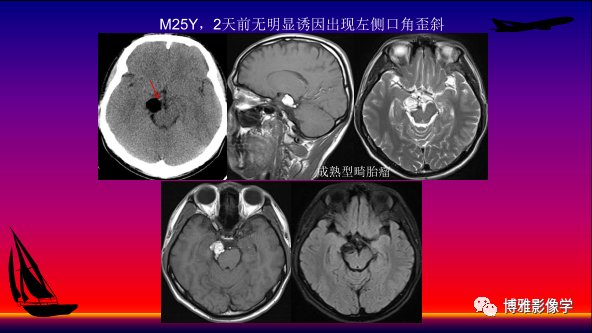

中枢神经系统病变基本成分信号特点